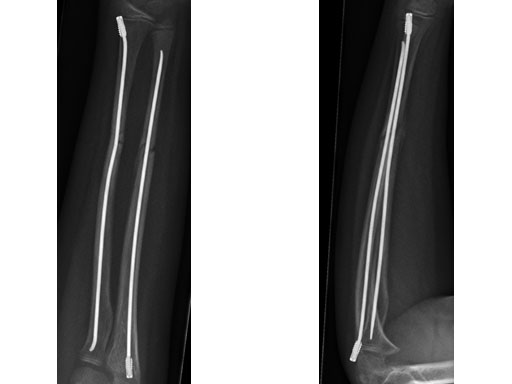

Case 1: Transverse forearm, shaft fracture (22D/4.1), 9-year-old girl.

Case provided by Theddy Slongo, Bern, Switzerland